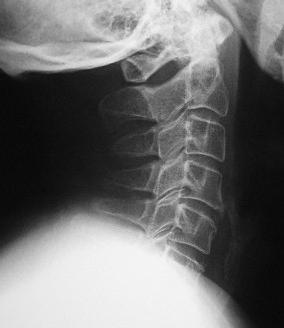

Problemas de cervicales

Cómo prevenir y aliviar el dolor de cervicales